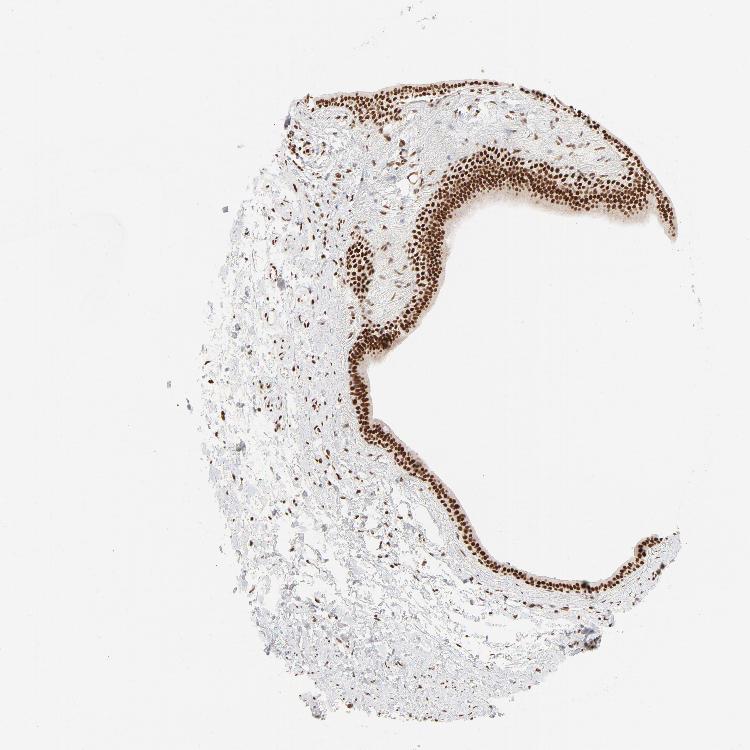

SOFT TISSUE 1 - Antibody stainingi

Antibody staining in the annotated cell types in the current human tissue is reported as not detected, low, medium, or high, based on conventional immunohistochemistry profiling in selected tissues. This score is based on the combination of the staining intensity and fraction of stained cells.

Each image is clickable and will lead to virtual microscopy that enables deeper exploration of all samples and also displays staining intensity scores, fraction scores and subcellular localization as well as patient and tissue information for each sample.

Antibody HPA017284Antibody CAB003703

Chondrocytes -Medium

Fibroblasts LowHigh

Peripheral nerve LowMedium